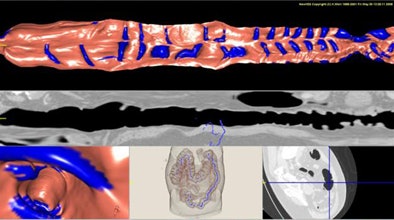

Except for the smallest structures, nearly all of the haustral folds were detected, "including 81.7% (1,326/1,624) of haustral folds, with 6.9 false positives per case," Oda said. "Sensitivity was higher than a previous method," he said.

![]() |

| The results show detected haustral folds marked in blue. |

| Most false positives were generated by small branches of sheetlike structures. Most false negatives resulted from thin haustral folds. |

In the previous study, published in 2000, Sato and colleagues proposed a sheet structure enhancement filter. The method succeeded in detecting haustral folds with a sensitivity of 76.3%, but it led to overdetection of haustral folds in areas of CT images that were sandwiched between colonic wall regions, Oda said of the study (IEEE Transactions on Visualization and Computer Graphics, April-June 2000, Vol. 6:2, pp. 160-180).

The present study, using an RSE enhancement filter, succeeded in detecting the ridges of the haustral folds with greater sensitivity than the previous study. However, further refinements will be needed to take full advantage of the data generated, Oda said.

One drawback of the current method, for example, is that thin areas of the colon wall between two different parts of the colonic lumen are overdetected, he said. Because local intensity structures of these thin-walled areas are similar to those of haustral folds, these regions need to be removed from the detection to eliminate most of the remaining false positives, he said.